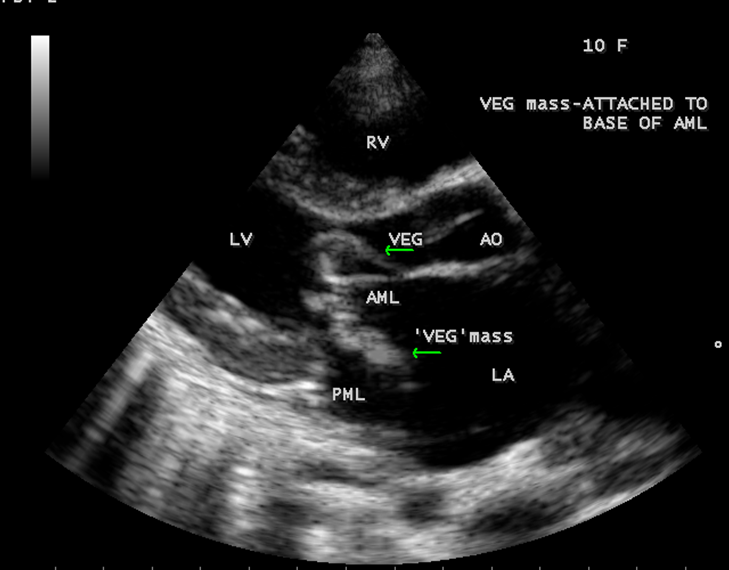

A 10 year female child was referred for echocardiographic evaluation with an apical systolic murmur. The child was having recurrent episodes of rheumatic fever (febrile illness with joint pains) at the age of 5-6 years and taken some treatment from the local medical practitioner, but she was not taken penicillin prophylaxis earlier. The child was remained afebrile for long period and no precipitating factors of infective endocarditis such as dental or genitourinary procedures in the past. General examination revealed normal growth and development, no cyanosis and clubbing and peripheral signs of infective endocarditis such s Osler’s nodes, Janeway lesions, Roths spots and splinter haemorrhages are not present and they are relatively rare in children. Physical examination revealed a grade 3/6 , blowing, high pitched, holosystolic murmur with a constant intensity and duration on dynamic auscultation and loudest at the apex with a radiation to left axilla and transmitted to the left infrascapular area and vertebral coloumn and it is due to the flow generating the murmur is directed posterolaterally within the left atrial cavity, suggesting the murmur of mitral regurgitation due to the rupture of chordae tendineae of anterior mitral leaflet. Blood culture revealed normal. Blood chemistry revealed the positive serum ASO titer, suggesting a recent streptococcal infection and other parameters are normal. X- ray chest reveled moderate cardiomegaly and ECG revealed a left ventricular volume overload pattern of eccentric hypertrophy due to LV dilatation as a result of severe mitral regurgitation and a normal rhythm. Transthoracic echocardiography revealed a giant vegetation ‘popcorn’ like in Figures 1,3 and 4 and ‘cucumber’ like in Figure 2, mainly attached to base and apical portion of anterior mitral leaflet as shown in Figure 31 and manifested in various size and shapes as shown in Figures 1 to 33. A flail anterior leaflet with a disorganized mitral regurgitation jet as shown in Figure 16 and 21 and the posterior leaflet is embedded with vegetation and resulting in ‘kissing forms’ as shown in Figures 13, 14 and 15 in echocardiography imaging. Tricuspid valve is also thickened and calcified as shown in Figure 2 in addition to thickened and calcified mitral leaflets, suggesting an underlying rheumatic etiology predisposing to the formation of vegetation. The child was given 1.2 million units of intramuscular benzathine penicillin injection as a therapeutic and initial prophylaxis dose for rheumatic fever and advised every 3 weeks for life long. Small doses of digoxin and diuretics are also prescribed and advised early surgery (mitral valve replacement) Transthoracic 2D images are as in Figures 1 to 33 are given below

The most common and direct evidence of infective endocarditis is the vegetation and it begins as a microscopic focus of infection and gradually grows into a conspicuous mass. It is typically an irregularly shaped, highly mobile, echogenic mass attached to the free edge of a valve leaflet ( most commonly at the coaptation line) and tends to develop on the ‘upstream’ side of the valve leaflets ( ie, the ventricular side of aortic valve and the atrial side of mitral and tricuspid valves. They may be seesile or pedunculated, but usually has an oscillating or fluttering motion, a typical feature of most vegetations. Vegetation move with the leaflet in a more chaotic (‘oscillating’) manner and it may prolapse through the valve into the LV (left ventricle) as it opens as shown in Figures 3, 4 and 16 and into LA (left atrium) as it closing (Figure 5 and 6) . The mass of vegetation is typically homogeneous with echogenicity similar to that of the myocardium. The infectious process often alter the valvular structure and function. Extensive involvement of the leaflet may result in chordal rupture, leading to severe regurgitation as shown in Figure 21 . Direct and typical signs of RMCT (ruptured mitral chordate tendineae) were chain-flail or whiplash-like changes and had an incidence of 86.7%, causing severe regurgitation and mitral chordal rupture is the leading cause of flail mitral leaflet[30]. A large vegetation may obstruct the valve orifice as shown in Figure 1 and 2 , sometimes termed as “obstructive-type bacterial endocarditis” and producing a functional valve stenosis ( Ping-Pong mitral stenosis [31]) similar to left atrial myxoma as shown in Figure 29.

The size and shape of vegetation vary due to curling of vegetation. The size of vegetation in this child is 35.6 x 9.3 mm as in Figure 17 , 20 x 23.7 mm as in Figure 1 , 32.9 x 13.9 mm as in Figure 2 .

The shape of vegetation varies in this child as ‘popcorn’ like (Figures 1,3 and 4 ), rod-shaped (Figure ), basket shaped (Figure 7 )[33-Figure 13.3], ‘baby in hand’ appearance (Figure 18), ‘cucumber shaped (Figure 2 ) and a ‘bunch of plantain’appearance (Figure 33 ), ring shaped (Figure 19 }, bileaflet structure (Figure 9 )with bileaflet MR jet as shown in Figure 10 . and kissing forms (Figure 13 - parasternal long axis view, Figure 14 - apical four chamber view and Figure 15 - short axis view)